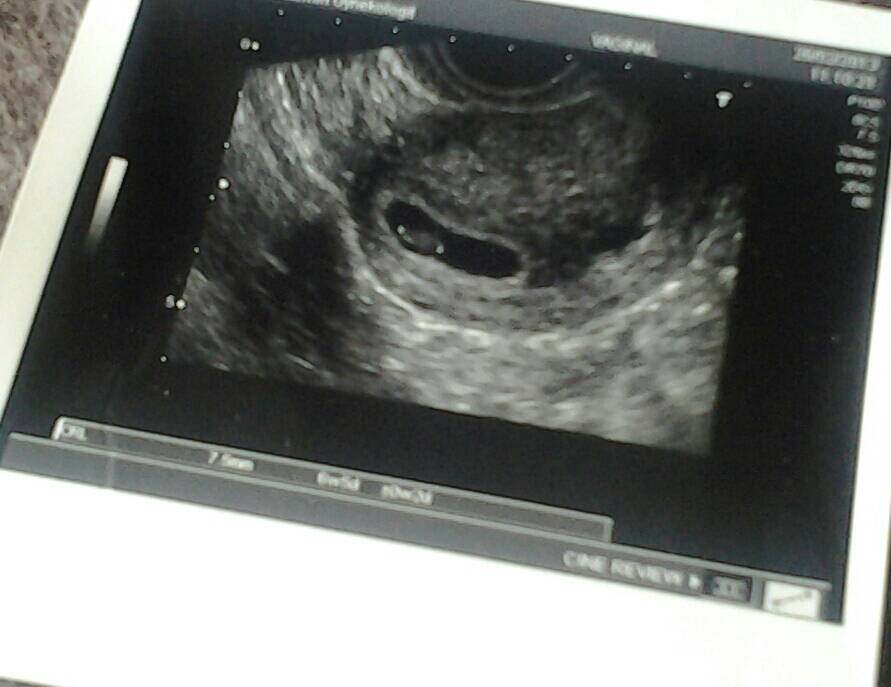

Lucky, mun mielestä toi sun piirtämä kuva näyttää kohdulta. Hitsi kun joudut oottelemaan maanantaihin asti vielä! Löysin kuvahaulla englanniksi jotain rv 6 ultrakuvia jotka näytti samalta kuin sinun piirtämä kuva.

Juu itse löysin kans Tollasen. Mutta mustan ympärillä olevat reunat oli paljon paksummat niinkuin kuvaan olen. Piirtänyt haalealla ja musta alue oli ohuempi enkä sisällä nähnyt mitään... ulkopuolella vain kun sauvaa liikautti ni näky sellanen kirkas vaalea piste.

Liitteet

• 1429865826642.jpg

1429865826642.jpg

48.6 KB · Katsottu: 208